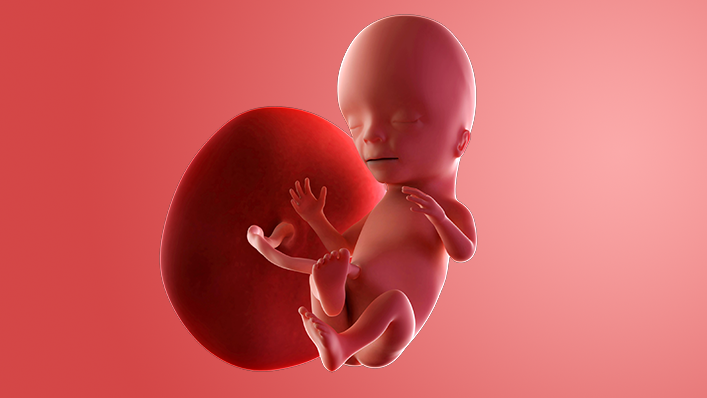

What does my baby look like?

Your baby, or foetus, is around 11.6cm long from head to bottom, which is the size of an avocado.

Your baby is starting to pull faces now, but any smiling or frowning will be completely random, as there's no muscle control yet.

The nervous system continues to develop, and this enables your baby to start moving their arms and legs. Your baby's hands can form fists and they may start punching around inside you too.

You might be able to feel your baby kicking from week 17 onwards.